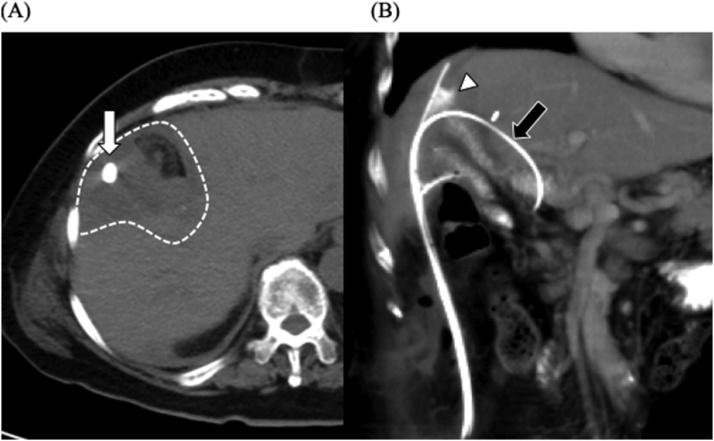

一名80岁女性,有远端胆管癌胰十二指肠切除术及辅助化疗史,出现胆漏。胰十二指肠切除术后6年,她因怀疑转移或肝内胆管癌接受了部分肝切除术。术后第9天,胆汁从引流管漏出,形成脓肿腔;这种情况一直持续到术后第28天。我们尝试在透视引导下,使用导丝和眼镜蛇型导管从肝脏切面进行选择性顺行引流。我们选择性地将胆管入口插管。引流20天后,脓肿腔消失。41天后,拔除引流管,患者出院。我们建议将此操作作为处理困难胆漏病例的一种可能的治疗选择。